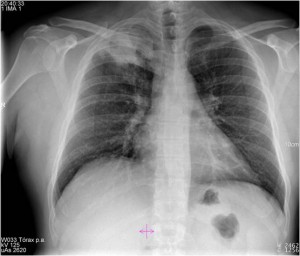

¿Qué hallazgos radiológicos se pueden observar en la imagen?